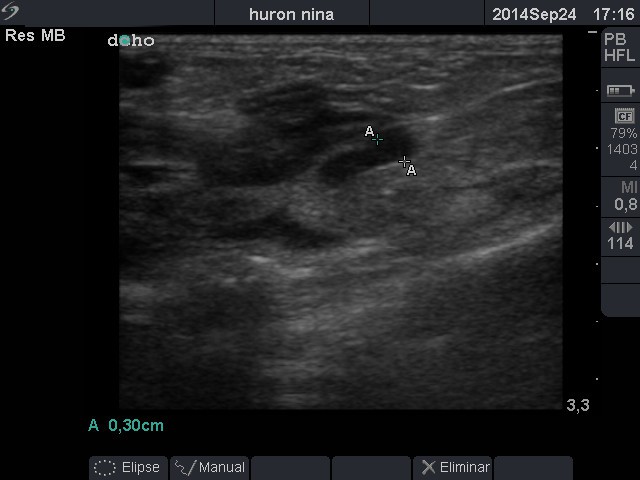

Glándula adrenal derecha anecogénica, tamaño 0,30cm; econormal.